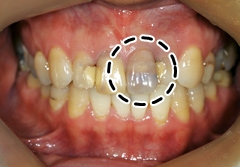

강한 충격에 멍이 든 앞니. 잇속 신경도 손상됐다. /에스플란트치과병원 제공

치아 내부에도 일반 피부 조직과 같이 모세혈관이 퍼져 있다. 치아에 순간적으로 센 힘이 가해지면 모세 혈관이 손상돼 출혈이 생긴다. 딱딱한 음식을 먹거나 실수로 숟가락를 씹었을 때, 단단한 물체에 치아를 부딪혔을 때다. 에스플란트치과병원 보존과 이향옥 원장은 "치아에 가해진 충격으로 잇속 신경이 죽고, 그로 인해 치아 내부 모세혈관이 터지면서 잇속에 멍이 생긴다"고 말했다. 치아 내부 출혈이 있고 한 달 정도 뒤부터는 혈액의 착색 정도가 심해지며 치아가 붉고 푸른색으로 변하다가 점차 거뭇해진다.